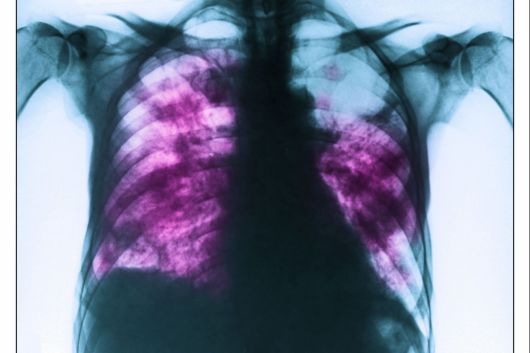

환자는 기존에 복용 중이던 약물이 없었으며, 피부보다는 눈, 입, 생식기 등 점막 중심의 증상이 두드러졌던 점이 주요 단서였다. 의료진은 혈액 검사 및 흉부 X선 검사를 통해 MIRM으로 최종 진단을 내렸다.